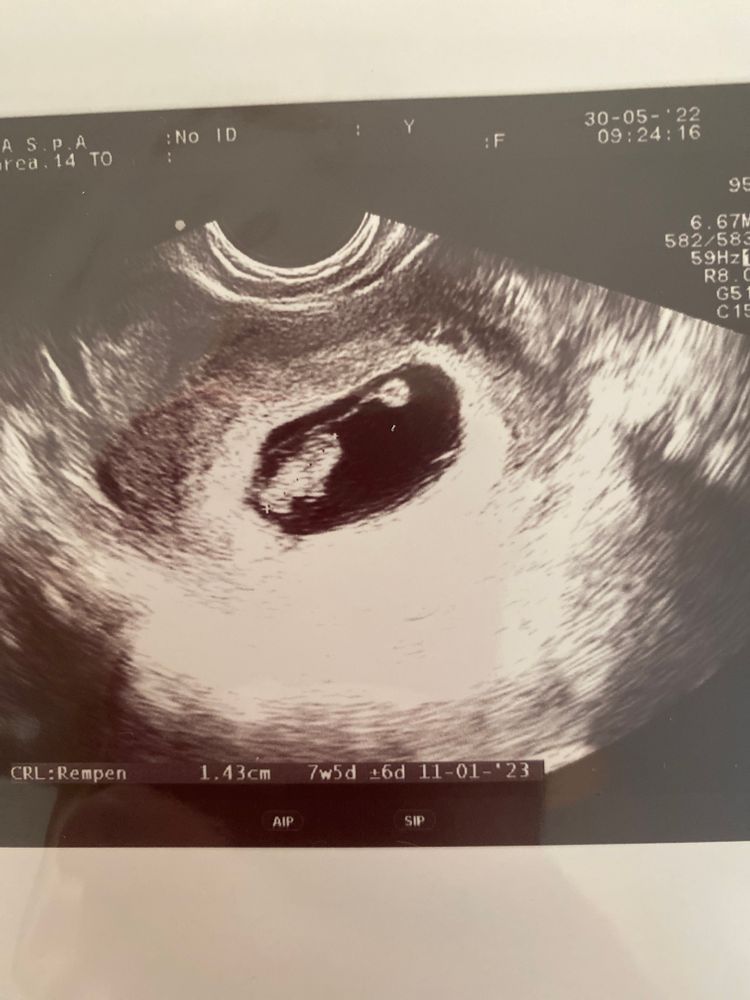

так есть какая то методика узи на 6 неделе , про расположению плаценты. Так же прикрепляю фото.

2 фото узи 6 недель